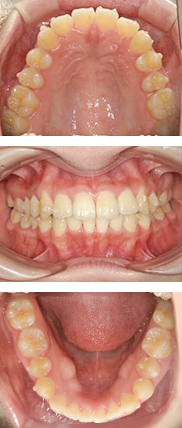

症例紹介

部分矯正症例

40代 女性

費用や期間の面で、全体矯正治療ができない方には、部分矯正治療を行う事も可能です。

ただし、追加でセラミック治療が必要になる場合もあります。

部分矯正治療費:54,000円

ジルコニアセラミック:108,000円(1本当たり)

矯正前

右上の前歯に、凸凹があり、むし歯で変色していました。

矯正中

右上の前歯3本に、透明なブラケットと白いワイヤーで部分矯正をしました。

矯正後

約4か月後には、前歯の咬み合わせが改善し、ジルコニアセラミックで、綺麗な前歯にしました。